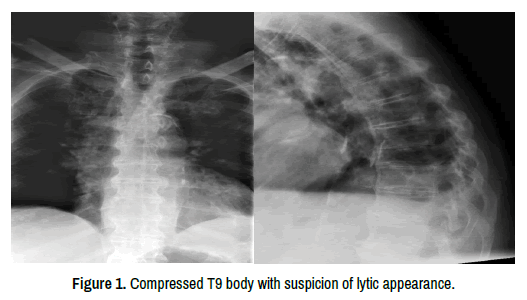

A 78-year-old man presented to the emergency department with intractable upper back pain, including night pain, and inability to mobilize due to pain. He had no significant medical background. On physical examination there was mid-thoracic midline tenderness and inability to change position in bed due to pain. Neurological examination was normal. Complete blood count and coagulation profile were normal, biochemistry revealed a slightly elevated creatinine of 1.22 mg/dL with normal calcium levels. Inflammatory markers were normal. Thoracic spine radiographs (Figure 1) demonstrated a compression fracture of T9. Computed tomography of the thoracolumbar spine (Figure 2) revealed lytic lesions in T8 and 9 with a pathologic compression fracture of T9. Defects of the T8 lower endplate and T9 upper endplate, as well as the T9 posterior wall, were noted. A very small lytic lesion was also observed in T7-not large enough to warrant intervention or cause concern of adjacent level fracture following treatment of T8.

Figure 1. Compressed T9 body with suspicion of lytic appearance.